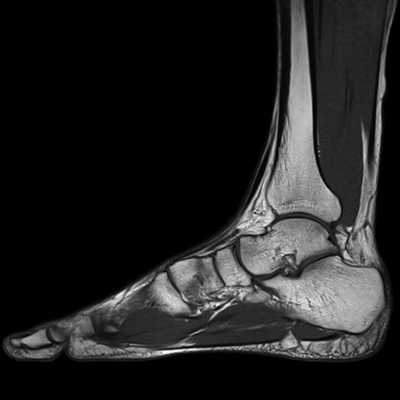

приходится до 25% от общего количества травм опорно-двигательного аппарата и 40-60% от числа повреждений нижней конечности. Диагностировать патологии области сочленения ноги и ступни можно с помощью рентгена, КТ и МРТ. Данные рентгенографии и компьютерной томографии в большей степени сфокусированы на визуализации костных тканей. Магнитно-резонансная томография явилась методом комплексной оценки повреждений голеностопного сустава и стопы. Её чувствительность в диагностике травматических повреждений и дегенеративных патологии в среднем составляет 98%, специфичность - 89%, точность - 94%. МРТ голеностопа позволяет получить четкие послойные снимки костей голеностопного сустава, хрящей, связочного аппарата, сухожилий, сосудов и окружающих их мягких тканей.

Что видно на МРТ голеностопа?

В ходе томографии голеностопного сустава оцениваются следующие анатомические аспекты:

- Взаимоотношения суставных поверхностей в голеностопном суставе и выпот стопы.

- Состояние подтаранного сустава.

- Проверяется, что медиальная и латеральная лодыжки не повреждены. Сухожилия задней и передней большеберцовых мышц, длинного сгибателя пальцев, длинной и короткой малоберцовых мышц не изменены или воспалены.

- Нет ли деформации и воспаления по ходу сухожилия задней б/берцовой мышцы.

- Дельтовидная связка носит целостный характер.

- Перонеальный удерживатель сухожилий не изменен.

- Передняя и задняя межберцовые связки не повреждены, щель межберцового синдесмоза равномерна и не расширена.

- Передняя малоберцово-таранная связка не определяется за счет отрыва от наружной лодыжки.

- Задняя малоберцово-таранная связка утолщена и разволокнена за счет растяжения и определяется на всем протяжении.

- Задний край таранной кости не деформирован.

- Пяточное (Ахиллово) сухожилие без патологических особенностей. Подошвенная фасция равномерно утолщена, а тарзальный канал не изменен.

- Собственно голеностопный и подтаранный суставы не деформированы.

- Мышцы не деформированы и однородны по интенсивности МР-сигнала.